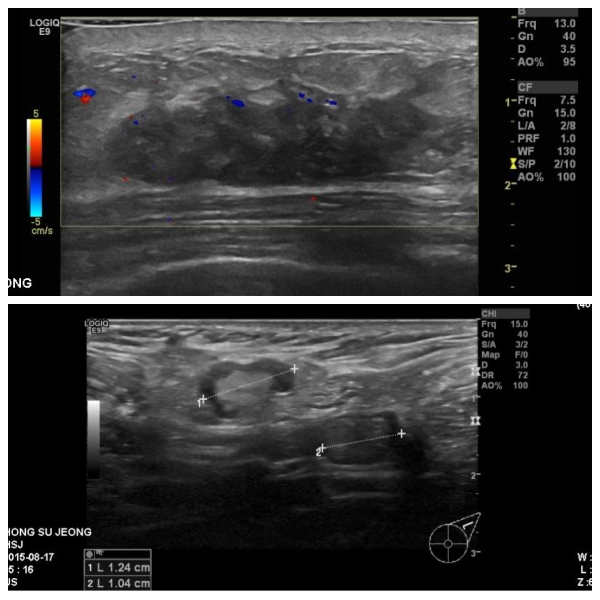

상기환자 40대 여자분으로 10년전부터 만져지는 멍우리 있었고, 최근 커지는 듯하여

본원에서 좌측유방조직검사와 좌측 겨드랑이 세포검사 시행한후, 좌측유방 침윤성 유관암과

겨드랑이 전이로 진단되셨습니다.